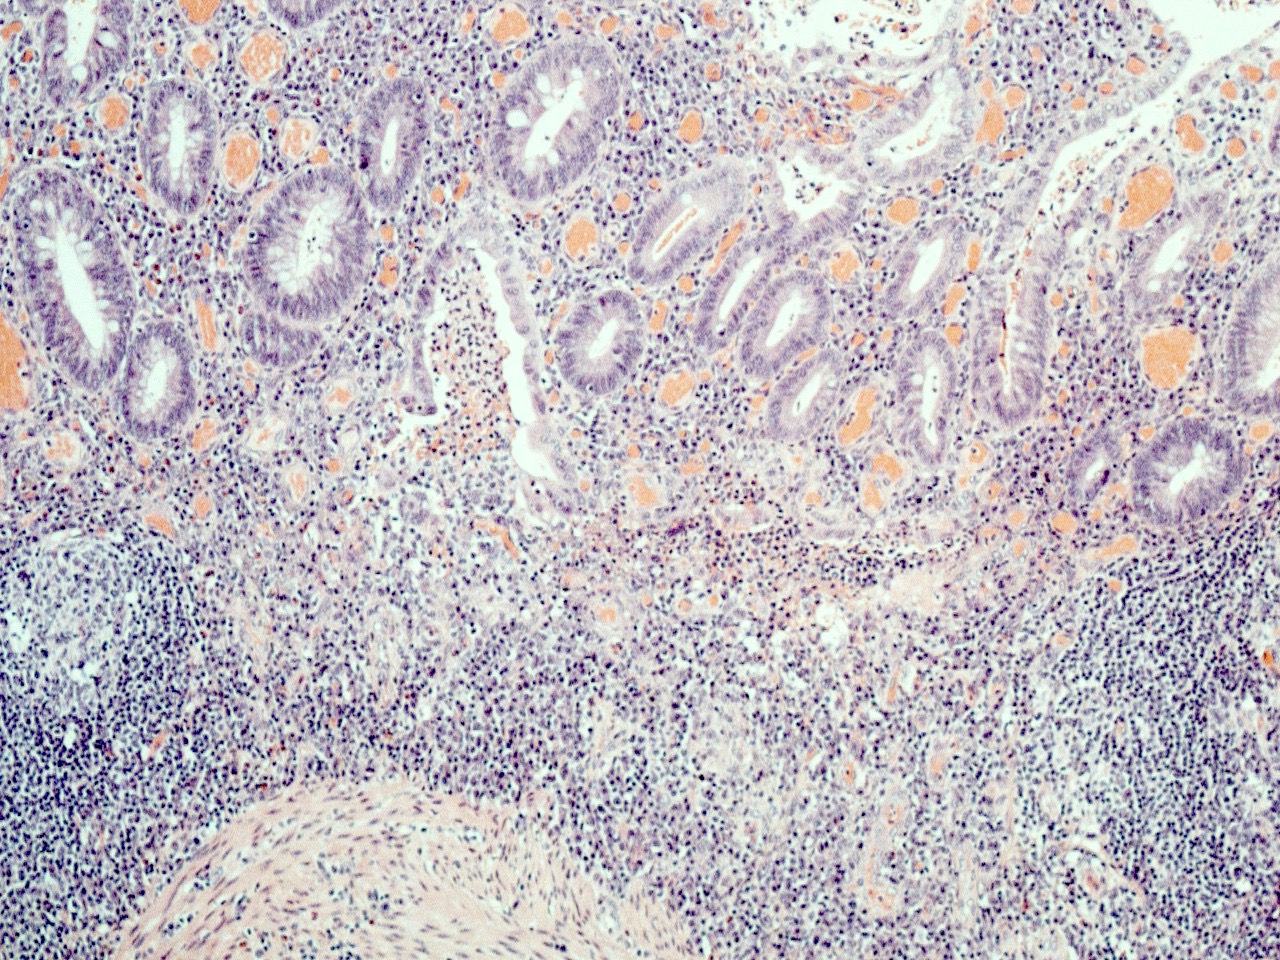

Microscopic (histologic) description

- Untreated disease characteristically shows active chronic colitis

- Features of chronicity include:

- Crypt architectural distortion including crypt atrophy, irregular spacing and size of crypts, crypt shortening and crypt branching

- Inflammatory expansion of the lamina propria with basal lymphoplasmacytosis

- Paneth cell metaplasia or hyperplasia

- Features of activity

- Neutrophilic inflammation with cryptitis, crypt abscess or ulceration

- Patients who have had symptoms for a short duration, longstanding disease or who have undergone therapy may have histological changes that may make microscopic diagnosis difficult (Histopathology 2014;64:317)

- Early / evolving cases may lack features of chronicity

- Treated cases may show chronic inactive (quiescent) colitis

- Superficial inflammation limited to mucosa / submucosa, with lack of transmural inflammation

- Lack of granulomas

- Crypt rupture granulomas may be noted

- Lack of fissuring ulcers

- Cases of fulminant ulcerative colitis may show fissuring ulcers and transmural inflammation (Am J Gastroenterol 2000;95:3184)

- Biopsies are limited in determining the depth of inflammation and the exact anatomical distribution of the inflammation (Histopathology 2014;64:317)

- Dysplasia (low or high grade) may be present, especially in patients with longstanding disease (Histopathology 2014;64:317)

- Activity is usually graded (Gastroenterology 2007;133:1099):

- Inactive: absence of neutrophils

- Mild: activity involving < 50% of the mucosa

- Moderate: activity involving > 50% of the mucosa; crypt abscesses usually seen at this grade

- Severe: presence of surface ulceration or erosion

- More complex grading systems, including Geboes and Robarts, exist but are not typically used in everyday practice (Gut 2000;47:404, Gut 2017;66:50)